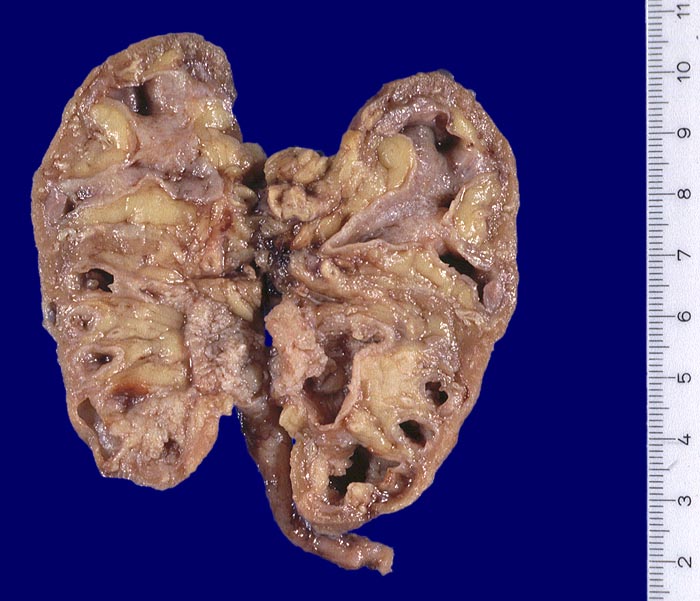

AP/ Urothelkarzinom bei Phenacetinabusus

Urothelkarzinom bei Phenacetinabusus

Pathomorphologisch unterscheiden sich Urothelkarzinome bei Phenacetinabusus nicht von sporadischen Urothelkarzinomen abgesehen von ihrer bevorzugten Lokalisation im Nierenbecken und der allenfalls ausserhalb des Tumors in der Harnwegsschleimhaut nachweisbaren Kapillarosklerose.

Morphologische Merkmale:

• Solider Tumor mit fokalen Entzündungsinfiltraten.

• Polymorphe Tumorzellen mit unscharfen Zellgrenzen und bläschenförmigen (=vesikulären) Kernen.

• Zahlreiche Mitosen.

• Ureter mit verdickten Kapillaren (Kapillarosklerose).